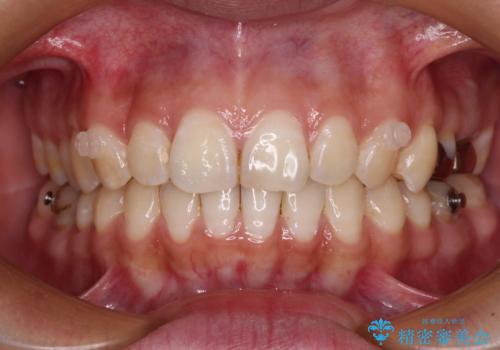

目立ちにくい装置を希望されていたため、ワイヤー装置とインビザラインを提案したところ、インビザラインを希望されました。

銀歯やムシ歯処置の必要な歯が奥歯にあり気になっていたので、矯正治療の途中でセラミッククラウンへ変更し、その後歯列を仕上げていくこととしました。

咬み合わせと目立っていた銀歯が改善され、患者様には大変満足していただきました。